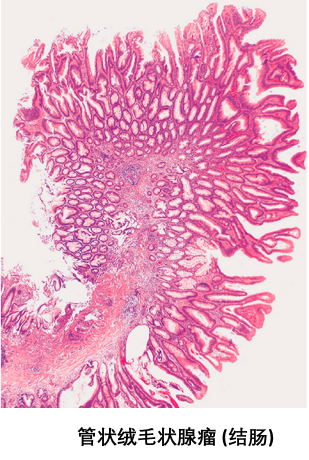

早期发现与及时治愈癌前病变,对肿瘤的预防具有重要的实际意义。临床上常见的癌前病变或疾病有以下几种:

4. 结肠、直肠的息肉状腺瘤; |